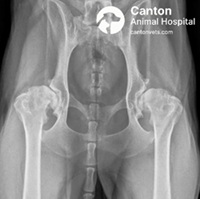

We perform Femoral Head & Neck Ostectomy (FHO) as a reliable, pain-relieving surgical option for dogs and cats suffering from hip-related conditions. FHO involves the removal of the femoral head and neck—the ball portion of the hip joint—eliminating painful bone-on-bone contact. This allows a “false joint” to form with surrounding soft tissues, providing pain-free mobility.

This procedure is especially beneficial for small to medium-sized dogs and cats with hip dysplasia, chronic luxation, femoral head fractures, or avascular necrosis. Though not an anatomical restoration like total hip replacement, FHO has proven highly effective with fewer complications and a more cost-conscious approach.